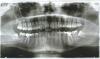

dixit Опубликовано 20 июня, 2011 Поделиться Опубликовано 20 июня, 2011 (изменено) Обратился к тремя врачам-ортодонтам в своём городе.Все трое дали разные варианты лечения:1. Либо брекеты только на верхнюю челюсть с удалением четверок (плохой вариант), либо на обе челюсти брекеты без удаления.2. Удаление верхних четверок, нижних восьмерок, потом брекеты на обе челюсти.3. Искривление не большое, необходимо носить трейнер около года, потом либо брекеты, либо достаточно постановки пластинки.Я, конечно, понимаю, что медицина самая точная наука после астрономии и философии, но разброс мнений пугает. На всякий случай: возраст 23, пол мужской, ранее никаких аппаратов для исправления прикуса не носил. Прошу Вашего совета. Изменено 20 июня, 2011 пользователем dixit Ссылка на комментарий

dixit Опубликовано 20 июня, 2011 Автор Поделиться Опубликовано 20 июня, 2011 Вот еще несколько снимков. верхняя челюсть сильно заходит на нижнююв нормальном состоянии Ссылка на комментарий

Премоляр Опубликовано 21 июня, 2011 Поделиться Опубликовано 21 июня, 2011 Да уж...варианты один лучше другого...8ки разумеется под удаление-это первое. Второе-на консультациях у докторов вам снимали слепки,расчитывали ТРГ???(ренген черепа сбоку)Третье-никаких трейнеров и лечения на одной челюсти. Только полноценное ортодонт.лечение. Более точные расчеты невозможны без ТРГ и анализа моделей, т.к. не видно смыкание боковой группы зубов Ссылка на комментарий